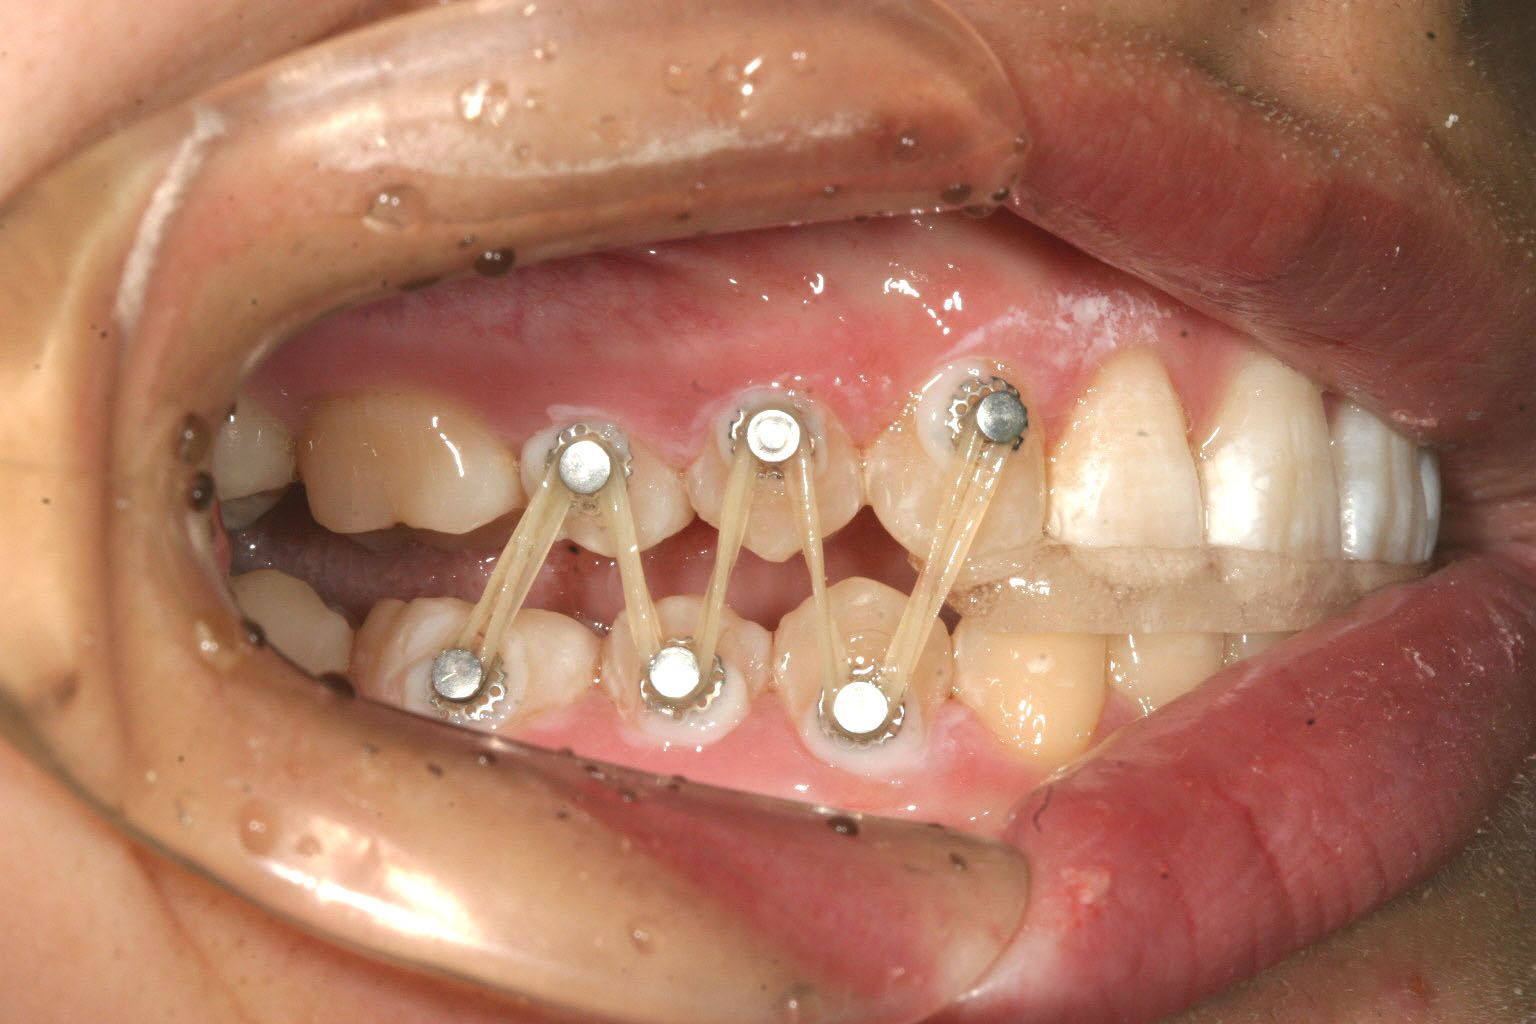

当院独自の自家製装置です。 前歯にジグを噛ませて臼歯に開いた隙間をゴムで閉じます。 この様にする事により結果的に下顎が前方移動し顎関節症が改善します。

今回のケースは顎関節症を伴う不正咬合でよく見かけるかみ合わせですが、上顎前歯が内に入っている為に下顎が後方へ押しやられその結果として顎関節に障害を生じていました。

この様な場合まずインビザラインにて上顎前歯をアーチ上に並べて下顎が前方に移動できる用意が出来たら正常咬合の位置で前歯部を固定する為、ジグを作成しそこで出来た臼歯の隙間をアップダウンエラスティックにて閉じると言う治療を行えば簡単に顎関節症の治療を行う事が出来ます。